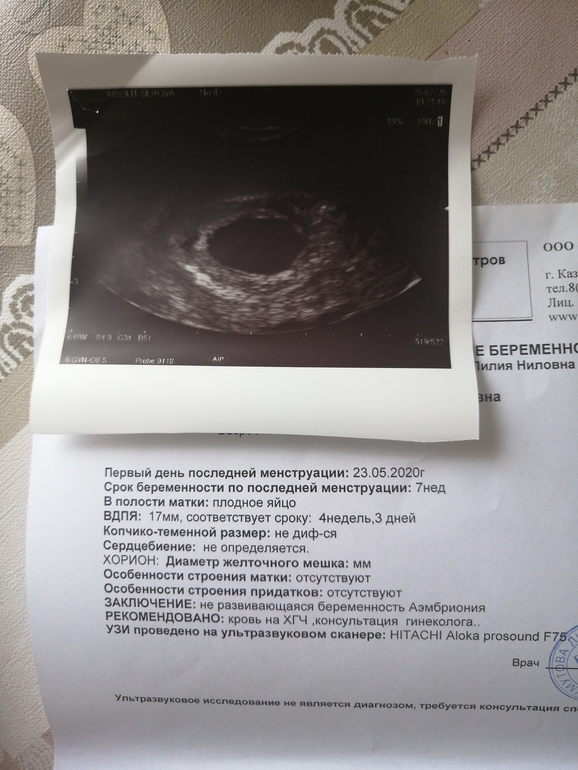

ФолликулометрияНе выдержила я до вс. Ни спать ни есть не могу. Чувствую что уже все нет шансов и чудо не произойдёт. По М сегодня у меня 7 недель и 5 дней. Пошла утром на узи и сказали что ничего там не видно. Что то мелькает но на таком сроке уже должно быть сб. Конечно она сказала подождать неделю но я не вижу смысла. Сдала хгч по рекомендации, вечером придёт результат. Отменяю утрик. Что мне делать дальше?

Очень жаль 😔 по размеру ПЯ видно, что не растёт ( попробуй отменить Утрик, само может выйти. Если не выйдет, то лучше МА

Отменять поддержку. Нормальная б выкарабкается, не нормальная есть все шансы что сама выйдет на отмене. По сроку к сожалению похоже на анембрионию.

Людмила Людмила, фактический срок беременности 4 недели, яйцо 1.7 см. Все само выйдет без всякого вакуума